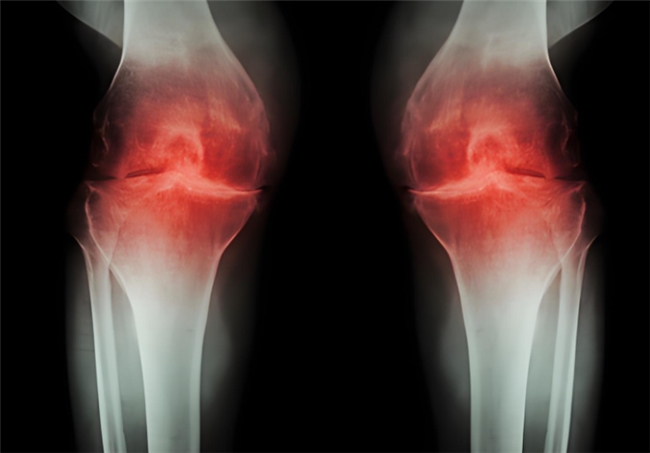

长期高油高糖、饮食不规律,很容易导致体重超标,而肥胖正是关节的 “隐形杀手”。多余的体重会让膝关节、髋关节等负重部位承受巨大压力,加速软骨磨损,久而久之,关节疼痛、僵硬、活动受限等问题接踵而至,大大增加骨关节炎的发病风险。而一旦患上骨关节炎是不可逆的,需要长期管理来延缓病情进展,氨糖就是临床常用,修复软骨、抑制损伤的优选。但它还有两种类型,到底盐酸和硫酸氨基葡萄糖有何不同?骨关节炎患者应该选哪个呢?

盐酸和硫酸氨基葡萄糖胶囊都是氨基葡萄糖类药物,能为关节软骨提供合成原料,在促进软骨基质的修复与再生的基础上,补充关节滑液以减少摩擦,同时通过抑制关节腔内的炎症因子,从多个方面帮助延缓骨关节炎的进展[1],但它们在临床疗效上却存在一定差异。

根据国际医学四大期刊之一《美国医学会杂志》上发布的一项研究表明,硫酸氨基葡萄糖在缓解膝骨关节炎疼痛、改善关节活动功能方面,效果优于盐酸氨糖等33种骨关节炎常用药[2]。还有相关研究显示,硫酸氨基葡萄糖不仅能延缓关节间隙变窄,还能从根源改善关节结构、减缓磨损。而盐酸氨基葡萄糖在这一关键指标上的效果尚未明确。因此,在关节保护的“确切性”上,硫酸氨基葡萄糖显然更具优势。